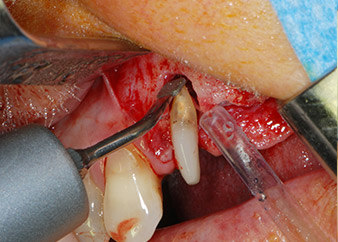

Въпреки това, ние се придържахме към първоначалния си план да запазим и двата зъба като абатмънти за временен мост по време на 6-месечната остеоинтеграция на имплантите. При повторна интервенция, ситуацията трябва да се преразгледа. Първо, в опит да се овладее ендо-перио проблема, останалата повърхност на зъба е внимателно обработена с пиезохирургично оборудване (Piezomed, W&H, използван с накрайник S1 под формата на шпатула, първоначално проектиран за ерозия на латералната синусна стена) (Фиг. 4).

След това апексът се изпилява със същия инструмент, за да се отстрани остатъчната инфектирана апикална тъкан и да се намали възможното допълнително усложнение по кореновите канали (апикоектомия) (Фиг. 5). Ретроградно запълване не е необходимо, защото ортоградното запълване току-що е ревизиран.